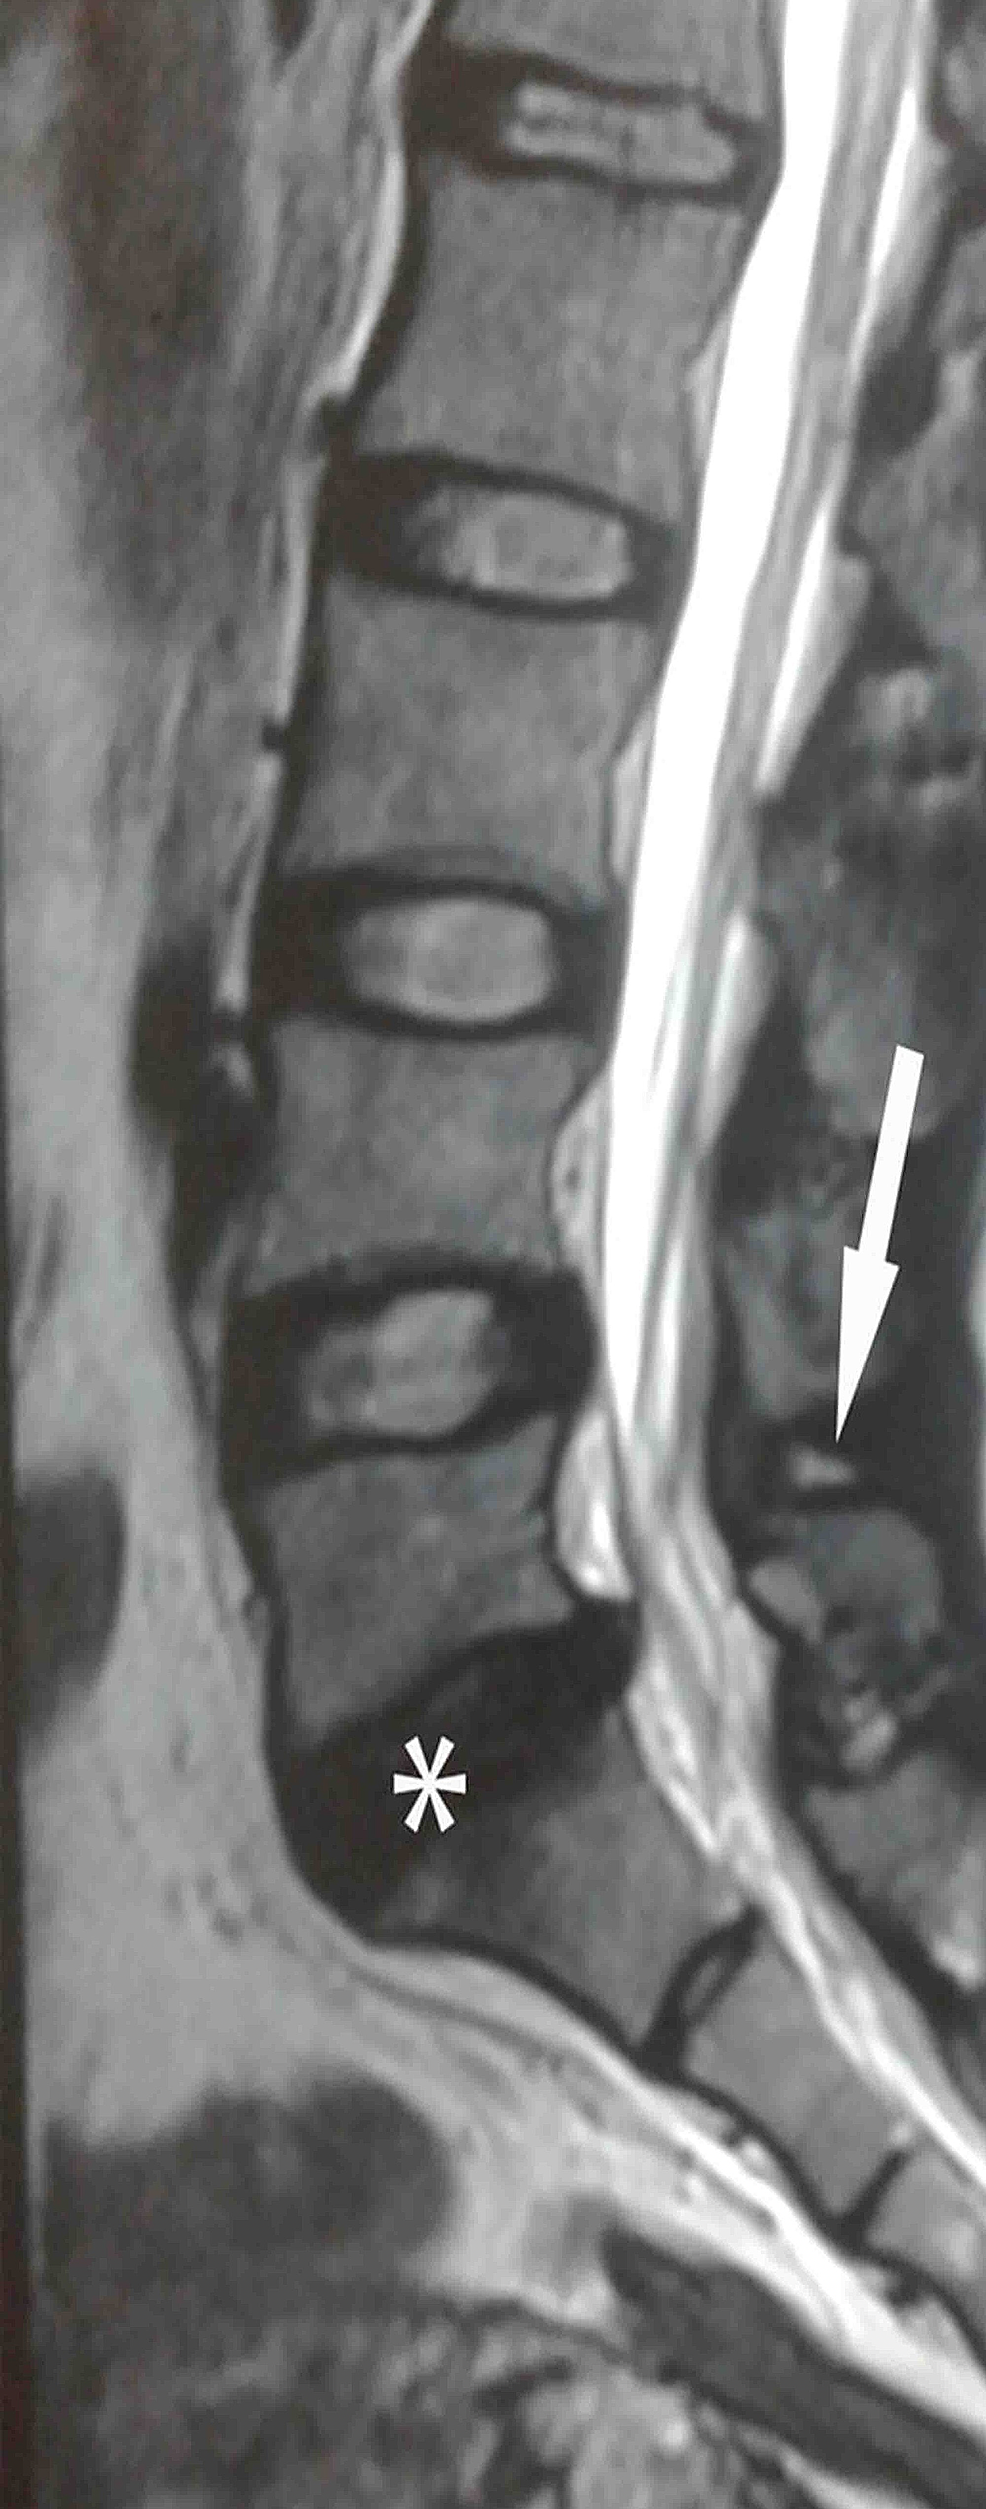

Lumbar Ligament Sprain-degeneration and Prolapsed Lumbar Intervertebral Disc: A Frequent Missed Combination | Cureus

image size: 986x2509